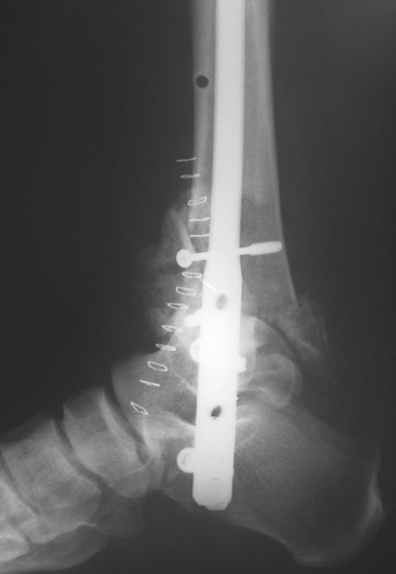

Nail arthrodesis for failed pilon fracture is good solution.

My example

В этом плане артродез на гвозде очень выигрывает - нет гипса, очень стабильная фиксация, нагрузку на ногу можно давать практически с первого дня и боли в значительной степени меньше т.к. операция малотравматична и фиксация стабильная. Конечно, методика не идеальна, не свободна от осложнений и имеет свои проблемы и нюансы.